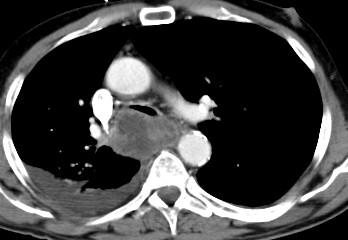

Au stade d'extention

metastatique du foie , poumon , plevre , surrenale ,

reins ,la CT scanner , echographie et medecine nucleaire PET

/CT sont en bien donner de resulta

Carcinome epidermoide 1/3 moyen de

oesophage . Image radiologique en TDM coupe

axiale et sagitale . |

Meme cas : image PET/CT

en coupe axiale a travers tumeur . Tumeur en situ et

extention ganglion hilaire |